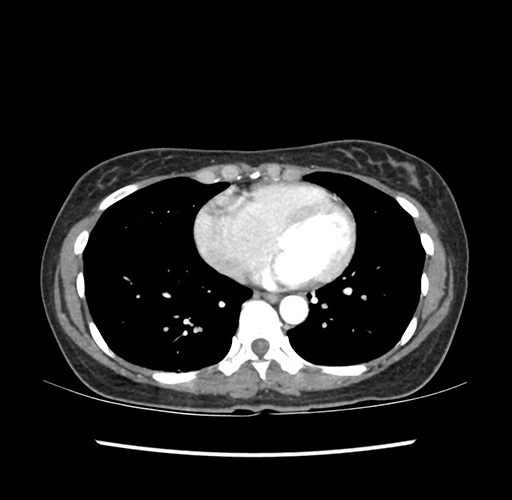

Imaging Analysis

Look through the patient's CT scan to identify any areas of concern for the necessary procedure.

Based on your CT findings, which issue(s) would give reason for "planned slowing down moment(s)" in this case?